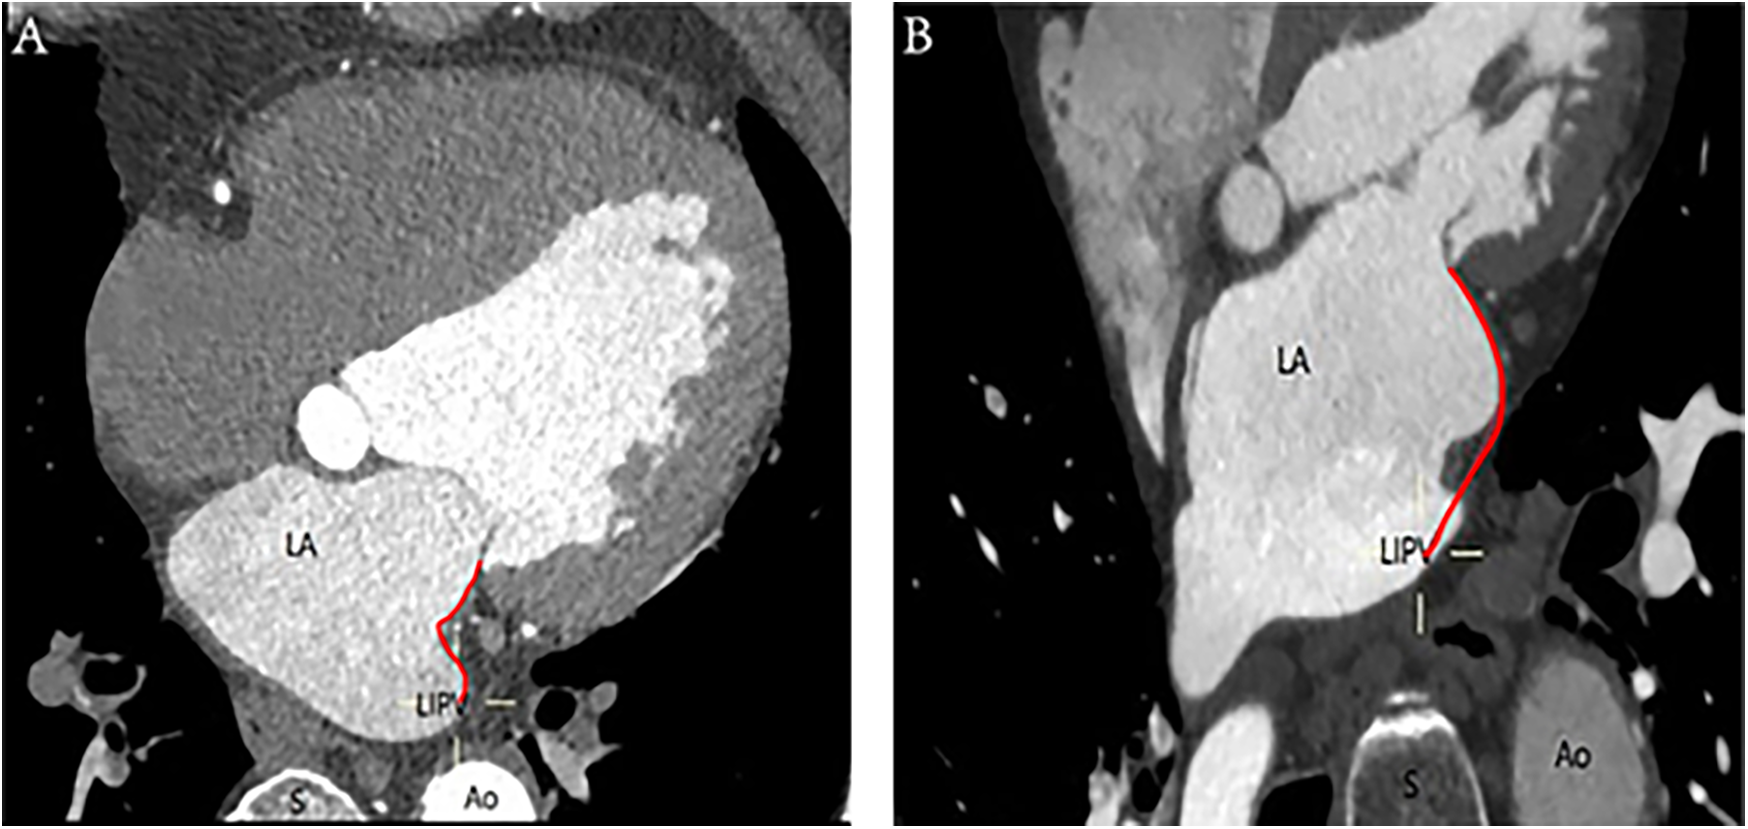

A ridge-shaped MI is identified when the endocardial contour prominently extends along a vertical line, forming a slender band on the surface. Conversely, the pouch-shaped morphology comprises the vestibule and the pouch, enhancing the granularity of the anatomical characterization of the MI, as depicted in Figure 2.

Figure 2

Ridge-shaped and pouch-shaped MI: (A) The left image depicts a ridge-shaped MI, whereas (B) the right image illustrates a pouch-shaped MI. The annotations are as follows: Ao, aorta; LA, left atrium; LIPV, left inferior pulmonary vein; S, spine; red curve, distance of MI.